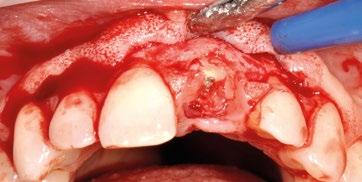

Fase quirúrgica: apertura del colgajo.

Previa anestesia se levanta un colgajo en sobre con incisiones convergentes hacia la pieza a extraer, a espesor mixto. Las papilas se inciden a espesor parcial, el colgajo se levanta a espesor total hasta 3 mm apical a la cresta ósea, donde se incide el periostio para seguir a espesor parcial, y poder así pasivizar y coronalizar el mismo. (Fig. 8 y 9).